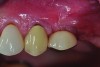

Fig 7. Four weeks following nonsurgical treatment, the area is healthy as probing depths are now shallow and bleeding is absent. Treatment involved scaling of the area, which removed all plaque and a slight amount of cement, and irrigation with an anti-inflammatory hydrogel.

Figure 7